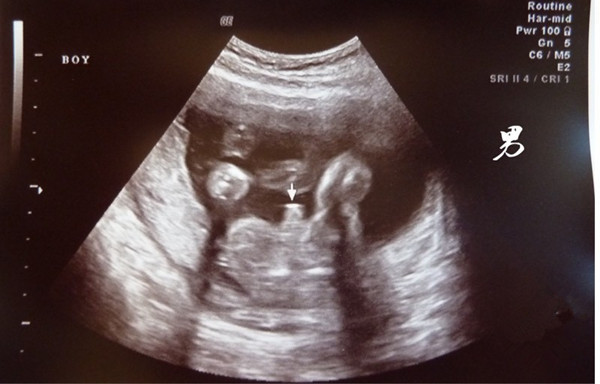

其实 , 要知道自己怀的是男孩还是女孩通过孕期症状来分辨是不准确的 , 所谓的症状其实会因人而异 , 而要说准确率最高的 , 还得是b超 。 就通过b超看胎儿性别是目前最靠谱的方法 , 虽然在医院看性别是违法的 , 但是一些孕妈还是非常幸运的看到了自己宝宝的性别 , 据说如果b超有这两点基本是男孩没跑了 , 具体是哪两点呢?

一、看亮点和白线分辨男孩女孩

在做b超的时候如果有幸看到胎儿腿部间有两个或者三个亮点的话 , 基本怀的就是男孩 , 如果b超时看到是三条白线 , 大多数怀的是女孩 。

这里的亮点 , 有宝妈说是男孩的睾丸血流型号 , 而白线更好区分了 , 女胎的大小阴唇 。 除此外 , 如果胎儿双腿间有一团菌状物体的话基本是男孩 , 也有的说男孩小JJ像一个小茶壶和小乌龟 , 男孩的生殖器会凸出来 。